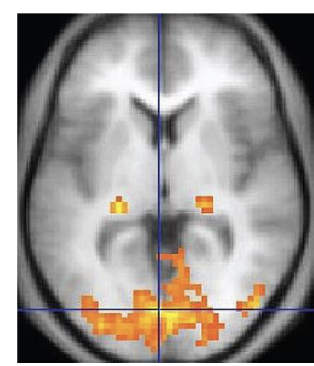

<p>Functional Magnetic Resonance Imaging (fMRI) </p>

Functional Magnetic Resonance Imaging (fMRI)

Is a non-invasive brain imaging that detects changes in blood flow and oxygenation in specific areas of the brain (epilepsy, tumors)